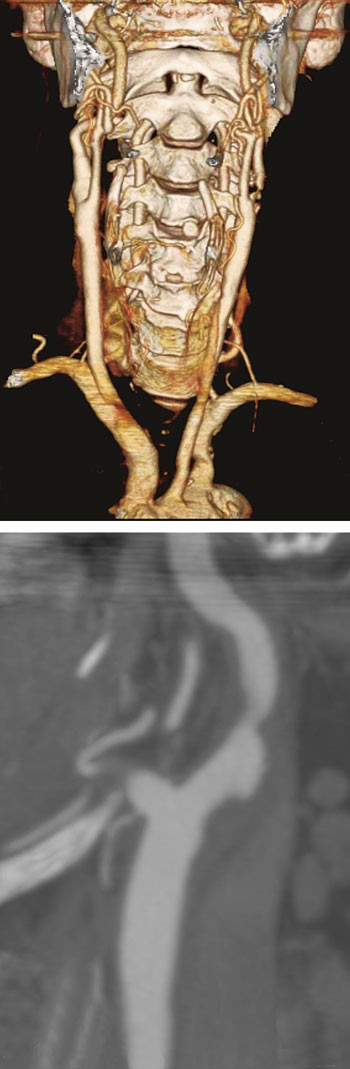

Hvordan beregnes stenosegrad?

Siden det er stenosegrad som bestemmer behandlingsindikasjon, er det viktig å se på hvordan denne måles. I ECST og NASCET ble stenosegrad angitt etter angiografi. Dette er en invasiv undersøkelse som i seg selv innebærer en risiko for slag på 0,1 % (5). I NASCET-studien angis stenosegrad som prosent diameterreduksjon i stenosen sammenliknet med diameter i a. carotis interna distalt for stenosen (fig 1). I ECST ble diameter i stenosen sammenliknet med en estimert ytre diameter (inkludert plakket) i bulbus caroticum. NASCET-metoden antas å være mer reproduserbar. Metaanalysen i Cochrane-databasen bruker formelen «ECST-measured % stenosis = 0,6 (NASCET-measured % stenosis) + 40 %» og tabeller for sammenlikning er publisert (tab 2) (6).

I de senere år har utvikling av MR- og CT-teknologi gitt nye muligheter for ikke-invasiv diagnostikk. CT-angiografi med moderne 64-kanalers spiral-CT gir detaljerte bilder av stenosen og forandringene i karveggen som tromber og kalk, og man får i samme skanning fremstilling av hele forløpet fra aortabuen til intracerebrale kar. Dette er nyttig i forhold til å vurdere egnethet for kirurgi eller stentbehandling. Hos oss henvises nå til ultralydundersøkelse av halskar som første screening, og CT-angiografi gjøres deretter som ledd i preoperativ planlegging. Vi benytter de aksiale originalsnittene til å måle karlumen og visualisere kalk, tromber og ulcerasjoner, for så ved hjelp av koronale og sagittale rekonstruksjoner å beregne stenosegrad på samme måte som ved konvensjonell angiografi (fig 3).